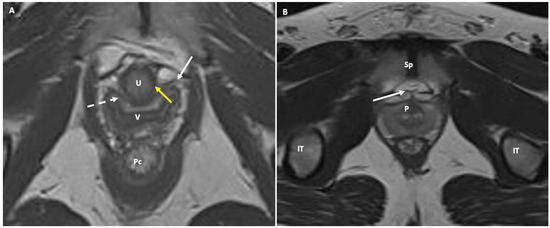

- Female urethra: This appears as a target-like structure, showing a central hypointense inner ring, which indicates the muscularis mucosa. Surrounding this is a middle, thicker ring of intermediate signal intensity, resulting from a combination of submucosa, longitudinal, and circular smooth muscle. The third, thinner hypointense outer ring represents the striated sphincter muscle. The surrounding space shows high signal intensity, representing connective tissue and smooth muscle within a highly collagenized vascular matrix. Within this space, three distinct ligaments can be identified at specific points along the urethra. At the 30th percentile, the periurethral ligament is visible as a thin hypointense linear structure originating from the medial aspect of the puborectal muscle, running ventrally to the urethra. The paraurethral ligament appears as a slightly oblique hypointense structure connecting the lateral wall of the urethra to the periurethral ligaments (Figure 4). At the 50th percentile, the pubourethral ligament is visible as a hypointense structure connecting the lateral aspect of the urethra to the arcus tendineus fasciae pelvis. In young males, corresponding structures may occasionally be visible in the retropubic space, just anterior to the prostate apex. On sagittal T2-weighted MR, the urethra appears as a cylindrical structure extending from the bladder neck to the external meatus. The signal intensity mirrors that described above, with the internal meatus as the zero point and the external meatus at the 100th percentile.

- Vaginal canal: From internal to external, the vaginal canal shows a high-signal intensity (due to mucous or secretions) surrounded by three layers with differing signal intensities: a low-signal-intensity inner layer corresponding to squamous keratinized epithelium and lamina propria; an intermediate-signal-intensity middle layer representing the muscular wall; and a low-signal-intensity outer layer representing loose connective tissue with its vascular supply.

- Anal sphincter complex: This shows variable composition and signal intensity on axial T2-weighted images depending on the level. The upper part consists of the internal sphincter, longitudinal muscle, and puborectal muscle. The middle part features the intersphincteric space, which appears as a high-signal-intensity, slit-like space between the internal sphincter (5 mm thick, intermediate signal intensity) and the external sphincter (1.5 mm thick, low signal intensity). A thin hypointense circular structure within this space represents the longitudinal muscle, which is a continuation of the outer longitudinal smooth muscle of the rectum. The lower part contains the external sphincter and the longitudinal muscle layer. On mid-coronal T2-weighted images, the thicker inner layer is formed by the two halves of the internal sphincter in apposition, while the intersphincteric space is visible as a thin, high-signal-intensity layer. At the outer margin, a cleft divides the puborectalis muscle (above) from the external sphincter (below). On midsagittal T2-weighted MR images, the anal sphincter appears as a low-signal-intensity, homogeneous, cylindrical structure, approximately 4 cm long, composed of muscle layers extending from the attachment of the levator ani muscle to the rectum. Lastly, the perianal spaces are clearly seen as two symmetrical, high-signal-intensity, fat-containing, pyramid-shaped spaces surrounding the hypointense anal canal, with multiple fibrous septa. The apex is visible at the origin of the V-shaped levator ani muscle, along with the supralevator space above it.